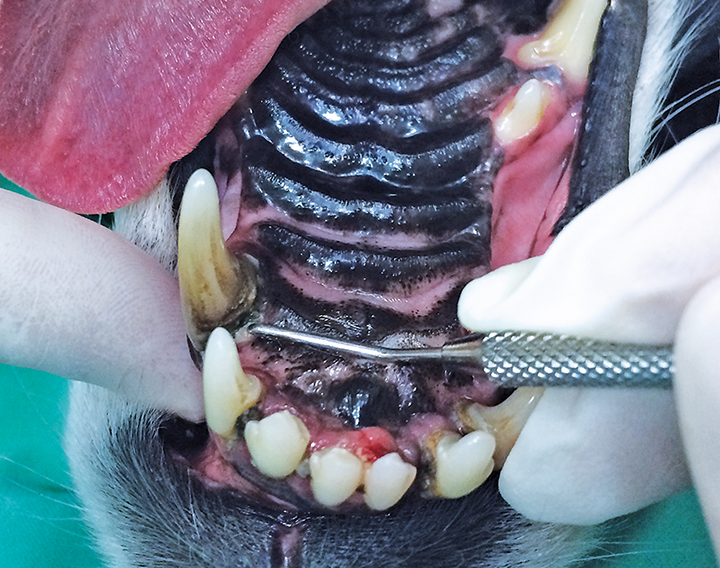

Canine mouth undergoing an anesthetic dental procedure.

FIGURE 1

With the patient under general anesthesia and in dorsal recumbency, dental charting and periodontal probing were performed on a tooth-by-tooth basis and revealed advanced periodontitis (PD4) at the right maxillary first and second incisor teeth and both maxillary canine teeth, with an oronasal fistula at the left maxillary canine tooth. The periodontal probe can be seen “disappearing” into the deep periodontal pocket/into the nose, which is characteristic of an oronasal fistula.

The oral cavity was rinsed with 0.12% chlorhexidine solution, and a complete oral examination using a UNC-15 periodontal probe and dental explorer was performed and supported by full-mouth dental radiographs. Detailed oral examination with the patient under general anesthesia confirmed bilaterally absent maxillary first and second premolar teeth (previously noted) with apparently intact soft tissue in the areas of missing teeth. Generalized moderate plaque and calculus accumulation were also confirmed and were associated with generalized moderate gingivitis. Mobility of 2 (ie, mobility over a distance of more than 0.5 mm and up to 1 mm)2 at the right maxillary first incisor tooth and mobility of 3 (ie, mobility over a distance exceeding 1 mm)2 at the right maxillary second incisor tooth with gingival recession of 4 mm and probing depth of 6 mm were diagnosed, confirming suspicion of advanced periodontitis. Physiologic mobility of a tooth is considered to be up to 0.2 mm, and normal/sulcal probing depth in a dog this size would be expected to be 1 to 2 mm.2 In addition, probing depth was >15 mm at the mesiopalatal aspect of the left maxillary canine tooth (Figure 1), which also had mobility of 1 (ie, mobility over a distance >0.2 mm and ≤0.5 mm)2; this had not been previously noted on the conscious examination. Bleeding from the left nostril occurred, which was suggestive of an oronasal fistula, likely the cause of the chronic unilateral nasal discharge. Probing depth at the mesiopalatal aspect of the right maxillary canine tooth was noted to be 10 mm, indicating advanced periodontitis at this tooth as well. The rest of the dental charting was within normal limits. Dental radiographs confirmed the clinical findings and revealed a retained root tip in the area of missing teeth (Figure 2).